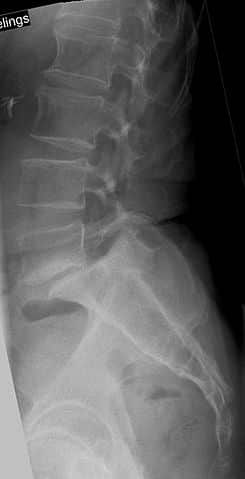

Спондилистез L5 над S1 виден на рентгенограмме.